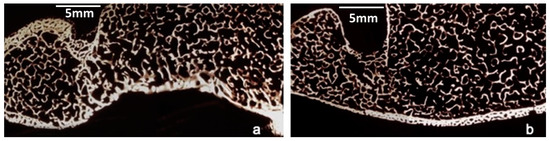

After 28 months, the histological examination of the 1st level of the right anterior flipper, removed after the animal’s death, showed mostly woven bone surrounding a wide medullary cavity with a thick layer of interposed fibrous tissue. Compact necrotic bone fragments could be identified inside the medullary cavity, showing numerous erosion cavities and surfaces (Figure 8a). No direct contact was observed between this necrotic bone and the newly-laid-down vital bone. The intermediate two levels (2nd and 3rd levels) presented three distinct tissues: vascularized woven bone, cartilage, and fibrous tissue. The newly-laid-down bone was often situated close to cartilaginous islands. These areas of cartilage tissue were densely populated with hypertrophic chondrocytes surrounded by a deep violet-stained capsule. A few large immature vascular cavities were observed within the cartilage next to the newly-laid-down bone (Figure 8b,c). At the 4th level, the primary bone formed an entire circular structure, in which a rough stratification was already appreciable. There were many large primary osteons presenting a thin, rather radio-opaque wall. The wide vascular channels of primary periosteal bone exhibited a prevalently radial direction, whereas in the internal layer the vascular channels were arranged longitudinally. Near the endosteum, secondary voluminous osteons were visible, delimited by evident cementing lines (Figure 8d). In some peripheral areas the cartilage was visible as a sheath surrounding the periosteal bone (Figure 8e). Fibrous tissue was observed at all levels.

3.3. Morphometric Findings

The diameters of the callus tissues were significantly larger than those of the control humerus diaphysis. In all the sections woven bone tissue neoformation was evident, though to a different degree at the various levels examined. At the proximal level (1st level), a complete bone sheath of compact, spongy tissue was present surrounding a wide medullary cavity, within which fragments of preexisting necrotic bone over extensive surfaces and with erosion cavities were clearly visible. On average, at the intermediate levels (2nd,3rd level) 20% of the space was occupied by compact bone with wide vascular channels, sometimes opening toward the periosteum, and 32% by cartilage, present largely on the medial side. Inside the medullary cavity there were still slight residues of preexisting necrotic bone. Finally, at the distal level (4th level), there was a complete compact bone sheath, partly stratified due to periosteal growth on preexisting bone portions, accounting for about 56% of the entire section. Moreover, in the preexisting bone, numerous secondary osteons could be seen (Figure 8f). The cartilage, which was sometimes calcified, extended over 6% of the surface, in a fairly thin layer confined to peripheral areas of the medial side of the callus. In the control bone the compact diaphysis occupied 74% of the section (Scheme 1).

3.4. The Epiphyseal Fracture

The histological and micro-radiographic examination of the epiphyseal fracture (5th level) showed complete fracture healing. Slight differences in shape and in microscopic structures were observed between the fractured and the healthy control humerus: the compact bone appeared slightly thickened (+ 31%) whereas the spongiosa appeared rarefied (−30%). Additionally, the fractured epiphysis showed a different outline, probably due to a reaction to the stainless-steel pins (Figure 9a,b). No cartilage or fibrous tissue were observed at this level (Scheme 2).

Figure 8. (a) microradiograph of the first level: the bone fragment shows numerous erosion cavities (white arrows). (b) histological findings at 2nd level. Three distinct areas are evident: fibrous tissue, woven bone, and cartilage. The white arrows point to wide immature vascular cavities within the cartilage next to woven bone (toluidine blue). (c) histological findings at 3rd level: the microphotograph shows a cartilage area densely populated with hypertrophic chondrocytes surrounded by an evident capsule. These islands are adjacent to the newly-laid-down bone (toluidine blu). (d) microradiograph of the 4th level: the photo shows an entire circular structure presenting a rough stratification. The red asterisk indicates more central mineralized (radio-opaque) areas with many visible osteons; the white asterisk shows peripheric cartilage impressions. (e) Histological section of the 4th level: peripherally are visible cartilaginous islands surrounding primary bone (violet-stained) (toluidine blue). (f) microphotograph of the 4th level: In the internal mineralized areas, secondary voluminous osteons are evident. (Green arrow) (toluidine blu).

Figure 9. Microradiographies examination of fractured (a) and healthy (b) epiphysis show complete fracture healing although slight differences in shape and microscopic structures.